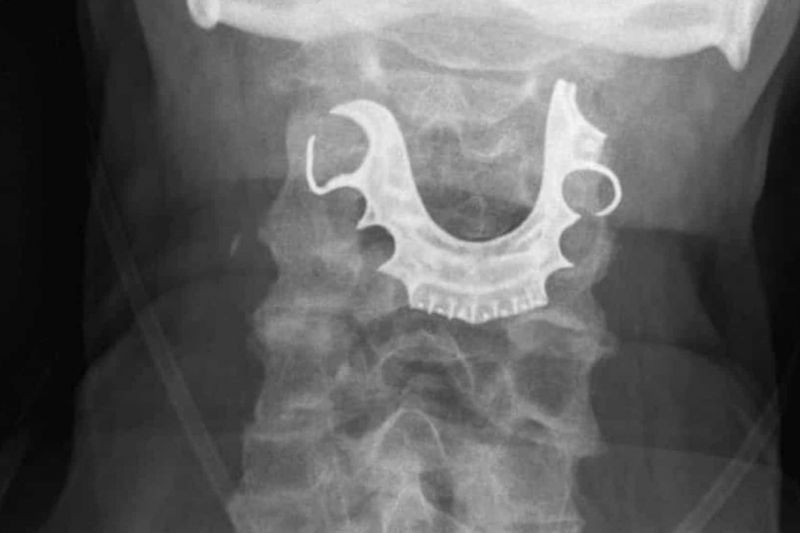

O problema deste britânico só foi detectado em uma segunda ida ao hospital, onde foi submetido a um novo raio-x que encontrou a dentadura alojada na garganta.

Durante os oito dias após a cirurgia o homem achou que tinha perdido a dentadura quando esteve internado no hospital.